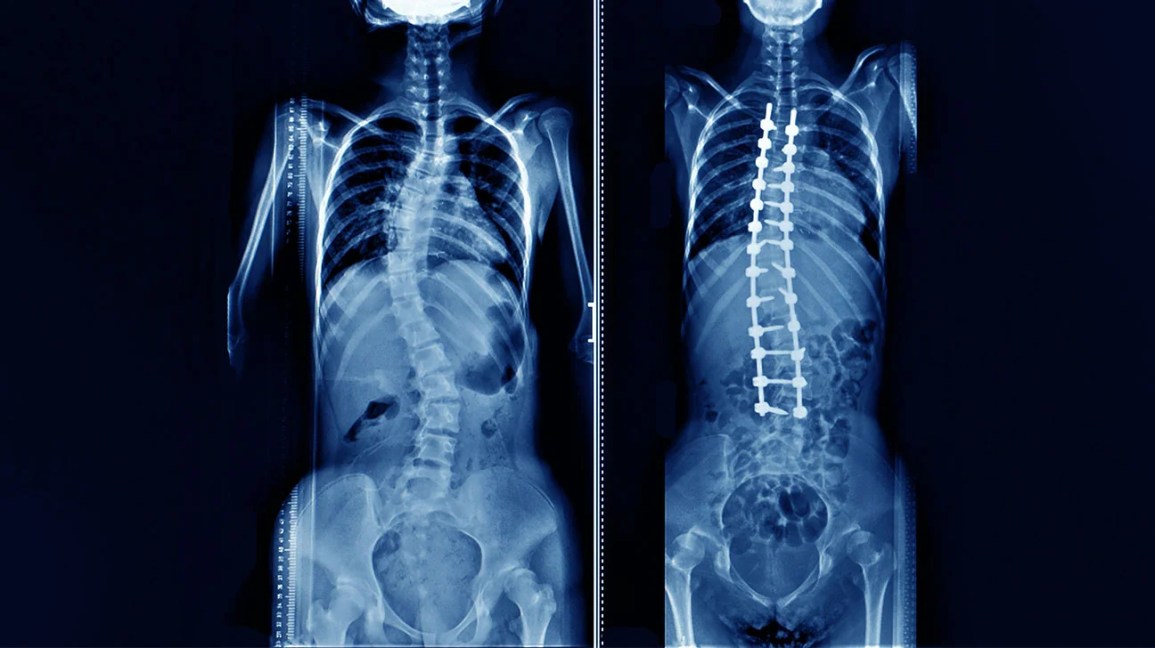

A escoliose, desvio na coluna que afeta cerca de 2% da população brasileira, vem ganhando novas […]